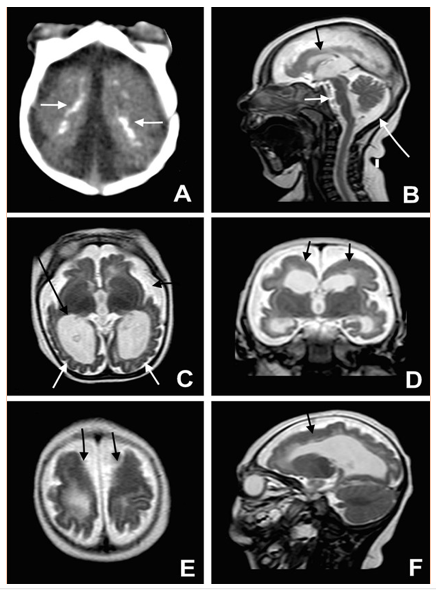

Figura 2. Fotografías A-F corteza cerebral delgada con grandes calcificaciones subcorticales, (A y B) así como cicatrices maculares criterios básicos para el diagnóstico radiológico complementario de Zika.